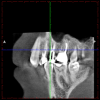

Born486 Опубликовано 23 мая, 2012 Поделиться Опубликовано 23 мая, 2012 Добрый вечер. Хотел бы получить совет специалистов. Интерисуют зубы под №14, 15, 16. Зубы не болят, но довольно сильно разрушены (были большие пломбы со штифтами, но со временем сломались стенки зубов (№15,16), лечение проводилось от 2-5 лет назад.Рекомендации от врачей:15 - зуб первый кандидат на удаление.16 - удаление или перепломбировка каналов (при помощи ультразвука) , резекция верхушки корня, штифтовкладка.14 - пока под вопросом.Ну вот как-то так! Ссылка на комментарий

kriokov Опубликовано 23 мая, 2012 Поделиться Опубликовано 23 мая, 2012 по КТ - 16 и 15 удалил бы. Ссылка на комментарий

Born486 Опубликовано 24 мая, 2012 Автор Поделиться Опубликовано 24 мая, 2012 16 -полностью перебрать.Сохранить можно.15 - 99.9% удалять14 - перебрать. Спасибо, за ответы, но хотелось бы подробнее про 15 зуб (какие видно проблемы по КТ) и 16 зуб насколько целесообразно сохранять его, сколько он может прослужить из Вашего опыта востановления подобных зубов (т.к. стоимость лечения выходит около 80-85% от стоимости установки имплантанта “под ключ”). Ссылка на комментарий